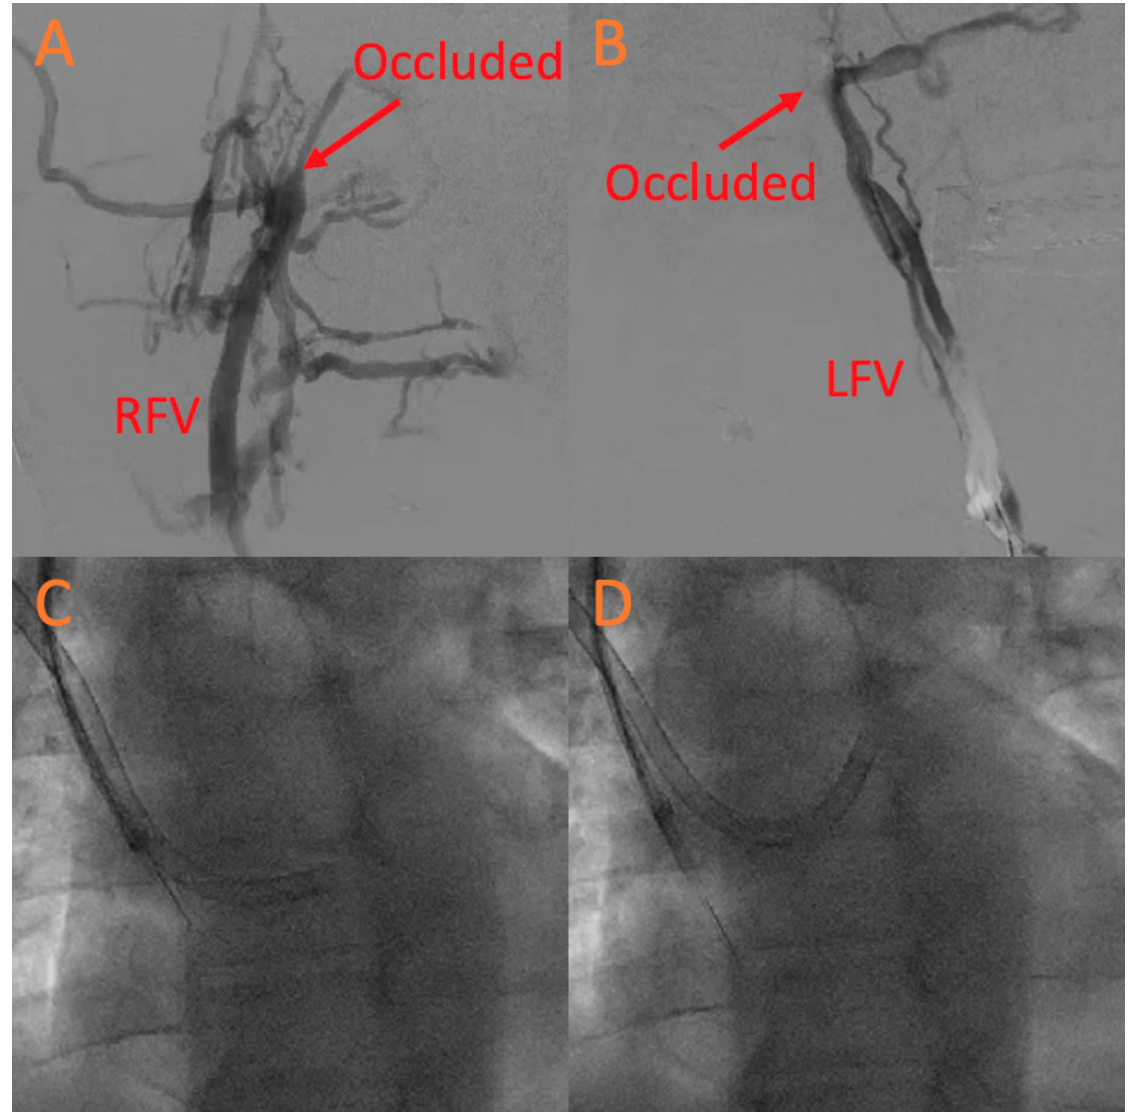

Bilateral femoral venogram was performed, confirming persistent chronic bilateral DVT (Figures 1A and 1B). Therefore, a transbrachial venous access approach was utilized. A right (12-Fr) and left (10-Fr) brachial vein access was obtained under ultrasound guidance. A 10-Fr intracardiac echocardiography (ICE) catheter (St Jude Medical) was inserted through the left brachial vein. The defect then crossed via the right brachial vein with an 8.5-Fr Agilis catheter (Abbott Cardiovascular) and exchanged for a 9-Fr 180 degree Amplatzer TorqVue sheath (St Jude Medical). However, the TorqVue sheath position was unstable in the left atrium with an unfavorable deployment angle. The intended 35-mm PFO device could fit into the Agilis sheath. Thus, a 12-Fr Oscor sheath (Oscor, Inc) was placed across the PFO (Figure 1C) under ICE guidance (Figure 1E). The Oscor sheath was then deflected upward for better alignment for PFO closure (Figure 1D). A 35-mm Amplatzer PFO occluder device (Abbott Cardiovascular) was deployed across the defect under ICE guidance (Figure 1F). Left brachial access (10 Fr) was closed with a pressure dressing, while right brachial access (12 Fr) was closed with a single Perclose device (Abbott Cardiovascular) and a pressure dressing. Postoperative transthoracic echocardiography showed stable device with no pericardial effusion.